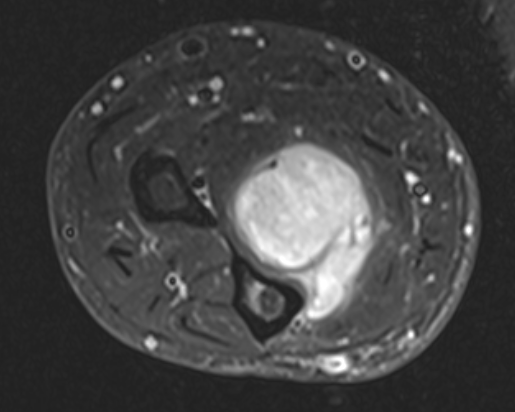

MRI

Anatomy / neurovascular involvement

Sarcoma medial thigh

Sarcoma anterior thigh

Sarcoma posterior thigh